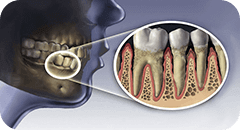

一般的な治療では神経をとった歯には金属の土台(メタルコア)をたてて補強します。その土台の形を整えてかぶせ物による治療を行うのですが、神経をとった歯は血液(栄養)の供給がなく周りの健康な歯とくらべるともろくなっていて必要以上の力が加わった場合、簡単に割れてしまいます。

メタルコア

歯根破折

ファイバーコア(しなりを持ったグラスファイバーと特殊樹脂でできた補強)は象牙質と同程度の硬さと柔軟性を持っていて強い力が加わった場合でも割れることなく歯を守ってくれます。

結果、隣の歯や咬み合わせの歯も健康な状態を保てることができ生涯トラブルの少ない健康なお口で幸せに過ごしていただくことができます。

ファイバーコア